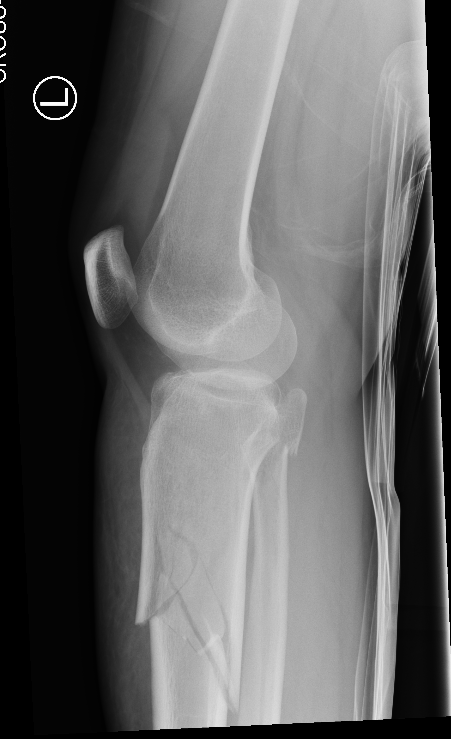

3. Supra-patellar approach with leg semi-extended

- flexed tibia tends to accentuate the deformity

- semi-extended reduces the deformity

- also easier to get lateral and posterior entry point

Smith & Nephew Semi-extended nail